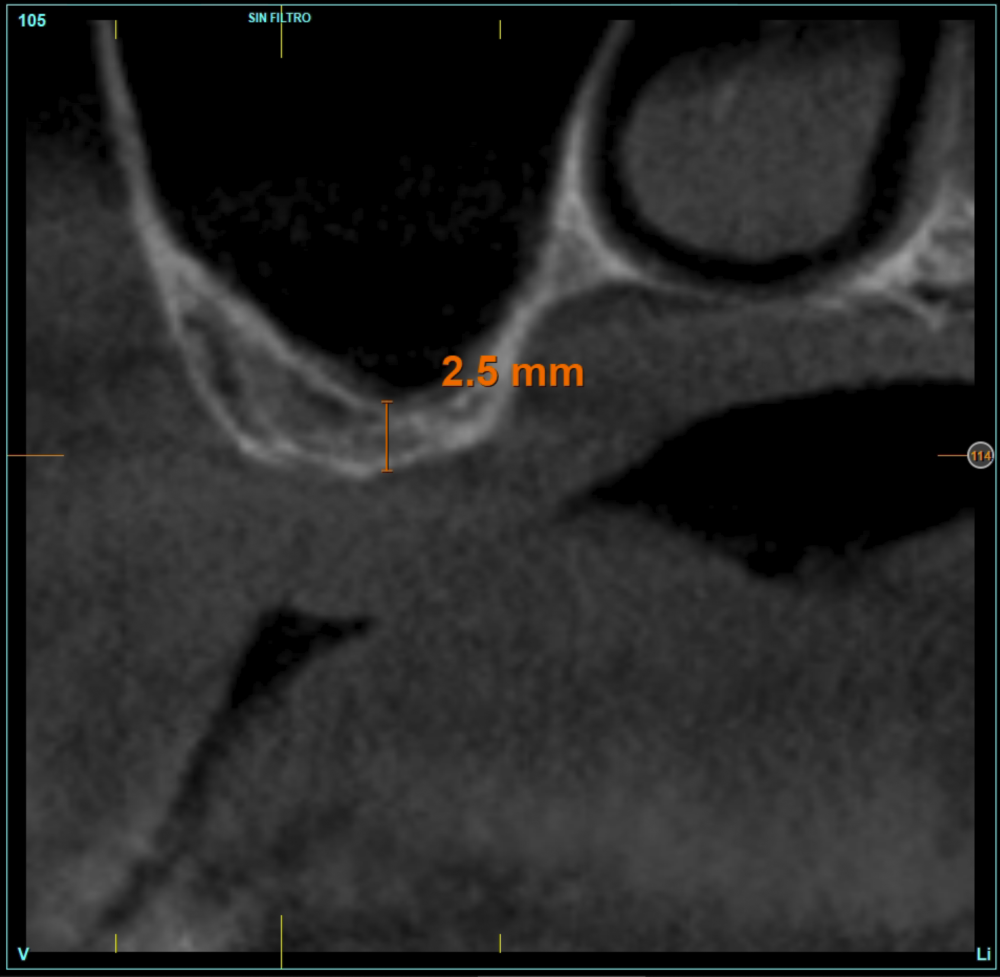

The mean height of the residual bone volume was 3.1 mm (+/- 0.3 mm with a range of 3-4 mm). In all cases, transcrestal sinus elevation was performed, with particulate autologous bone obtained from milling the neo alveolus generation zone for implant insertion, being the average of this elevation above the apex of the implant of 2.8 mm (+/- 0.99 range 1.9 -5 mm). In the CT control scan after one year of inserting the studied implants, the bone gain achieved was maintained, no decrease in the volume gained was observed, only three cases showed a decrease of between 0.4 and 0.5 mm of the initial volume at the end (Table).

Material and method. A retrospective study has been carried out in patients in whom extra-short implants (4.5 and 5.5 mm length) were inserted directly by transcrestal elevation with residual ridges between 2 and 3 mm. The implant was the analysis unit for the descriptive statistics regarding location, implant dimensions, and radiographic measurements. The patient was the measurement unit for the analysis of age, sex and medical history. The main variable was the gain in height over the apex of the implant after 6 months of the surgery and one year after the load comparing both measurements and as secondary variables the biological complications and the implant failure were recorded.

Patients attend subsequent check-ups performing a control Cone-Beam after 5 months (before loading the implant) and after one year of the load, performing a new measurement in these images to analyse the bone gain and the maintenance of the same. In these check-ups, data are collected on prosthetic complications or crestal bone loss in these patients, as well as possible failures.

Figures 2-19 show one of the cases included in the study.